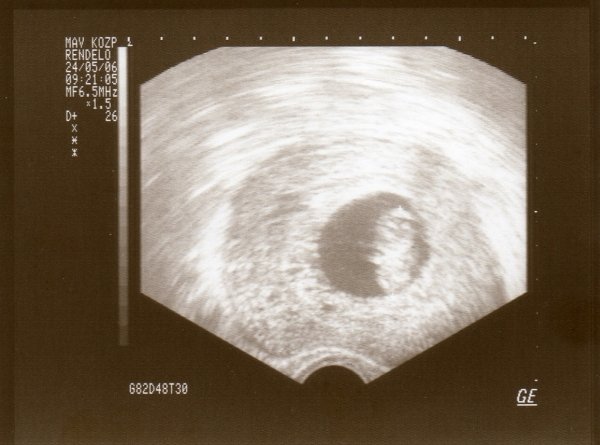

Bea! De jó, gratulálok Óriáskádhoz :D , olyan jó érzés lehet látni ahogy egyre csak nődögél :D . eddig csak hüvelyi ultrahangot csináltak?

Bea, nagyon örülök, hogy minden rendben volt :D ezek a legjobb UH-ok, mert itt még egyben látni az egész picurt. :lol: